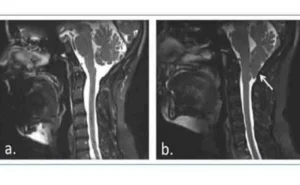

Мальформация Киари типа I подразумевает каудальное выпадение миндалин мозжечка примерно на 5 мм ниже большого затылочного отверстия, которое обычно не сопровождается опущением ствола мозга или четвёртого желудочка и не вызывает гидроцефалии, но связано с сирингомиелией.

Сирингомиелия вызывается образованием полостей или кист (сиринга или syrinx), заполненных жидкостью внутри спинного мозга, которые могут медленно расширяться, вызывая прогрессирующее повреждение спинного мозга и внутричерепную гипертензию из‑за давления, оказываемого этой жидкостью.

Самая крайняя форма заключается в грыжеобразном выпадении структур наиболее нижней части мозжечка — миндалин мозжечка — и ствола мозга через большое затылочное отверстие, так что некоторые участки головного мозга достигают спинномозгового канала, утолщая и сдавливая его.